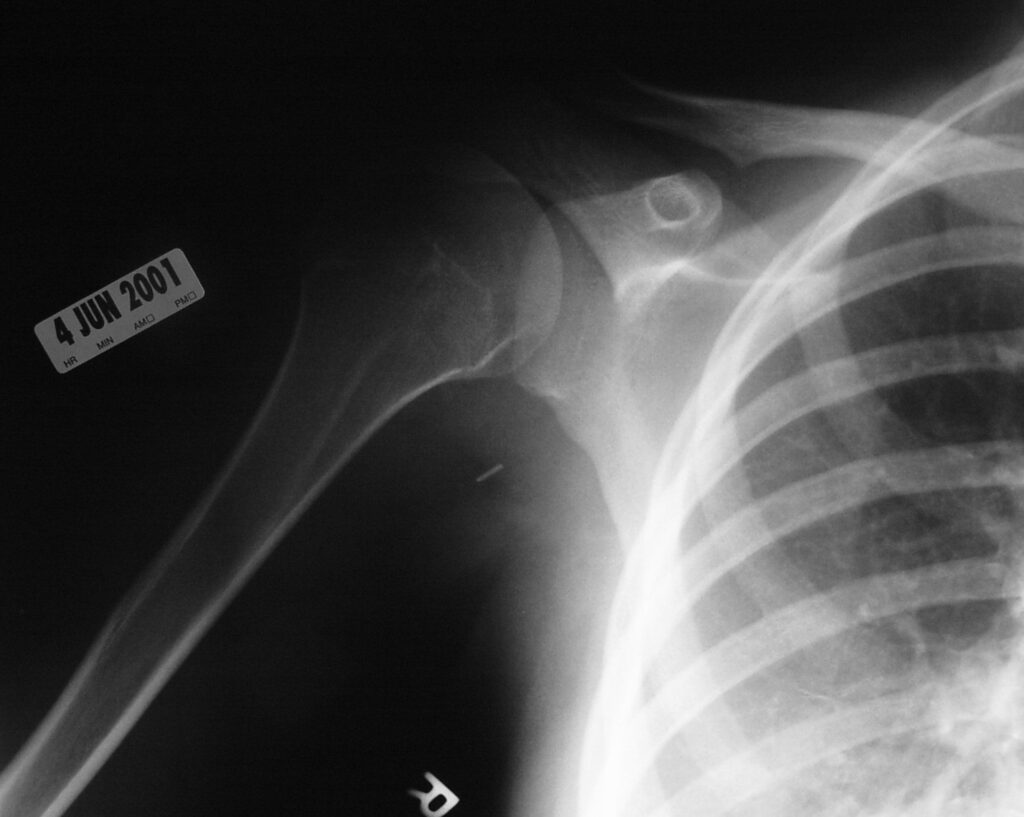

Synovial chondromatosis is an uncommon, benign, process that occurs in large joints, such as the knee (50%), hip, elbow, or shoulder. This process mainly affects synovium and hence most commonly arises from joints and tendons which are lined by synovium. Synovial Chondromatosis may also affect bursae and extend into surrounding soft tissues. This condition is seen in patients between 20 and 50 years of age and most commonly in men (male-female ratio of 2-4/1). The patient usually complains of pain, stiffness, crepitance, swelling, and joint locking. The knee is the most common site to be affected. Symptoms are long-standing and progressive. The plain x-ray may be normal (5 to 33%) or there may be small flecks of calcification (Fig. 1 & 2). On MRI the nodules of cartilage are easily seen. MR imaging may also show synovial thickening, joint erosions and intraarticular calcifications. The signal characteristics of these intraarticular bodies depend of their composition. If mineralization is not present the signal intensity follows the cartilage signal with intermediate signal on T1 images and high signal on T2 weighted MR images. Uniformly calcified bodies follows bone density on all sequences with bone marrow signal centrally and low signal peripherally (Fig. 3-5). Histologically the cartilage is arranged in nodules, which are quite cellular (Fig. 7-9). Synovial lining is present surrounding the cartilage nodules (Fig. 8). The cartilage nodules are often referred to as loose bodies however they are not really loose and embedded in the synovium lining. This is considered a metaplastic condition as opposed to a true neoplastic condition. Rarely it may turn into a malignancy usually a low grade chondrosarcoma. Malignant change is suggested by deep erosions into adjacent bone.

Fig. 1 & 2. Plain X rays of right shoulder synovial chondromatosis. AP (Fig. 1) and outlet (Fig. 2) views demonstrate multiple calcified bodies. Joint erosions are not seen on these x rays.